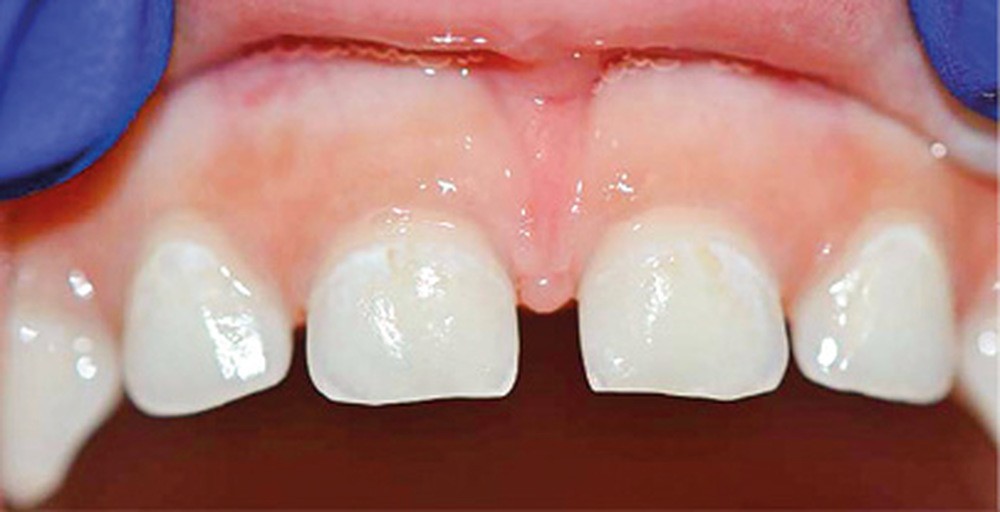

Dès l’atteinte d’une face de l’émail de la couronne dentaire, un traitement doit être proposé. Les traitements généralement conservateurs seront gradués selon la sévérité et l’activité de la lésion carieuse (fig. 1).

- La perte de chance pour le développement : la CPE non traitée va entraîner l’avulsion précoce de certaines dents, induisant des troubles alimentaires pouvant se répercuter sur le développement général de l’enfant (croissance et développement cognitif), voire de sa vie sociale (absences scolaires répétées, pas de sourire). La CPE a un impact négatif sur la qualité de vie de l’enfant.